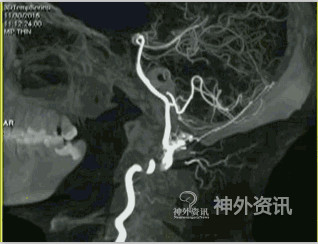

图5: 下颈段脊髓血管畸形,↑示畸形血管团。A、B. 2D-DSA;C. 3D-DSA;D~F. 静态最大密度投影(MIP)冠状位、矢状位和轴位融合影像。

图5: G. 动态旋转MIP融合影像。

图5: H~J. 静态双容积重建冠状位、矢状位和轴位融合影像。

图5: K. 动态双容积重建冠状位融合影像。

图5: L. 动态双容积重建矢状位融合影像。

图5: M. 动态双容积重建轴位融合影像。